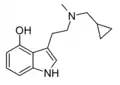

| McPT | artificial | H | CH3 | C3H5 | N-Methyl-N-cyclopropyltryptamine | 1373918-63-8 |